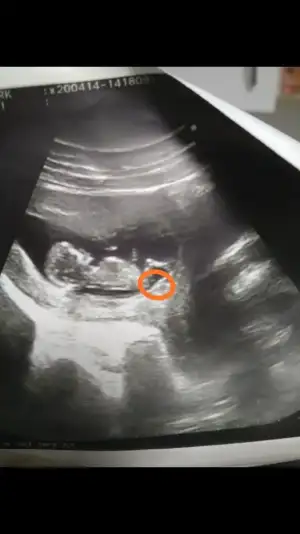

Sevgili arkadaşlar kaç gündür fotoğrafa filozof edasıyla bakıyorum resmen 😊 size de danışmak istedim yeniden, bu nub denilen çıkıntılı acaba benim ufaklikta daire içerisine aldığım çıkıntı mıdır? Eğer o kısım ise bu teoriye göre gerçekten kıza benziyor bizimkisi 🤗

• IMG_20200424_212411.webp

IMG_20200424_212411.webp

15,6 KB · Görüntüleme: 83